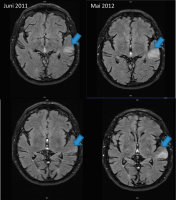

Abbildung 1: MRT/FLAIR vom Juni 2011 (radiologische Erstdiagnose) und präbioptisch im Mai 2012: zunehmende hyperintense Signalalteration links temporal (blauer Pfeil)